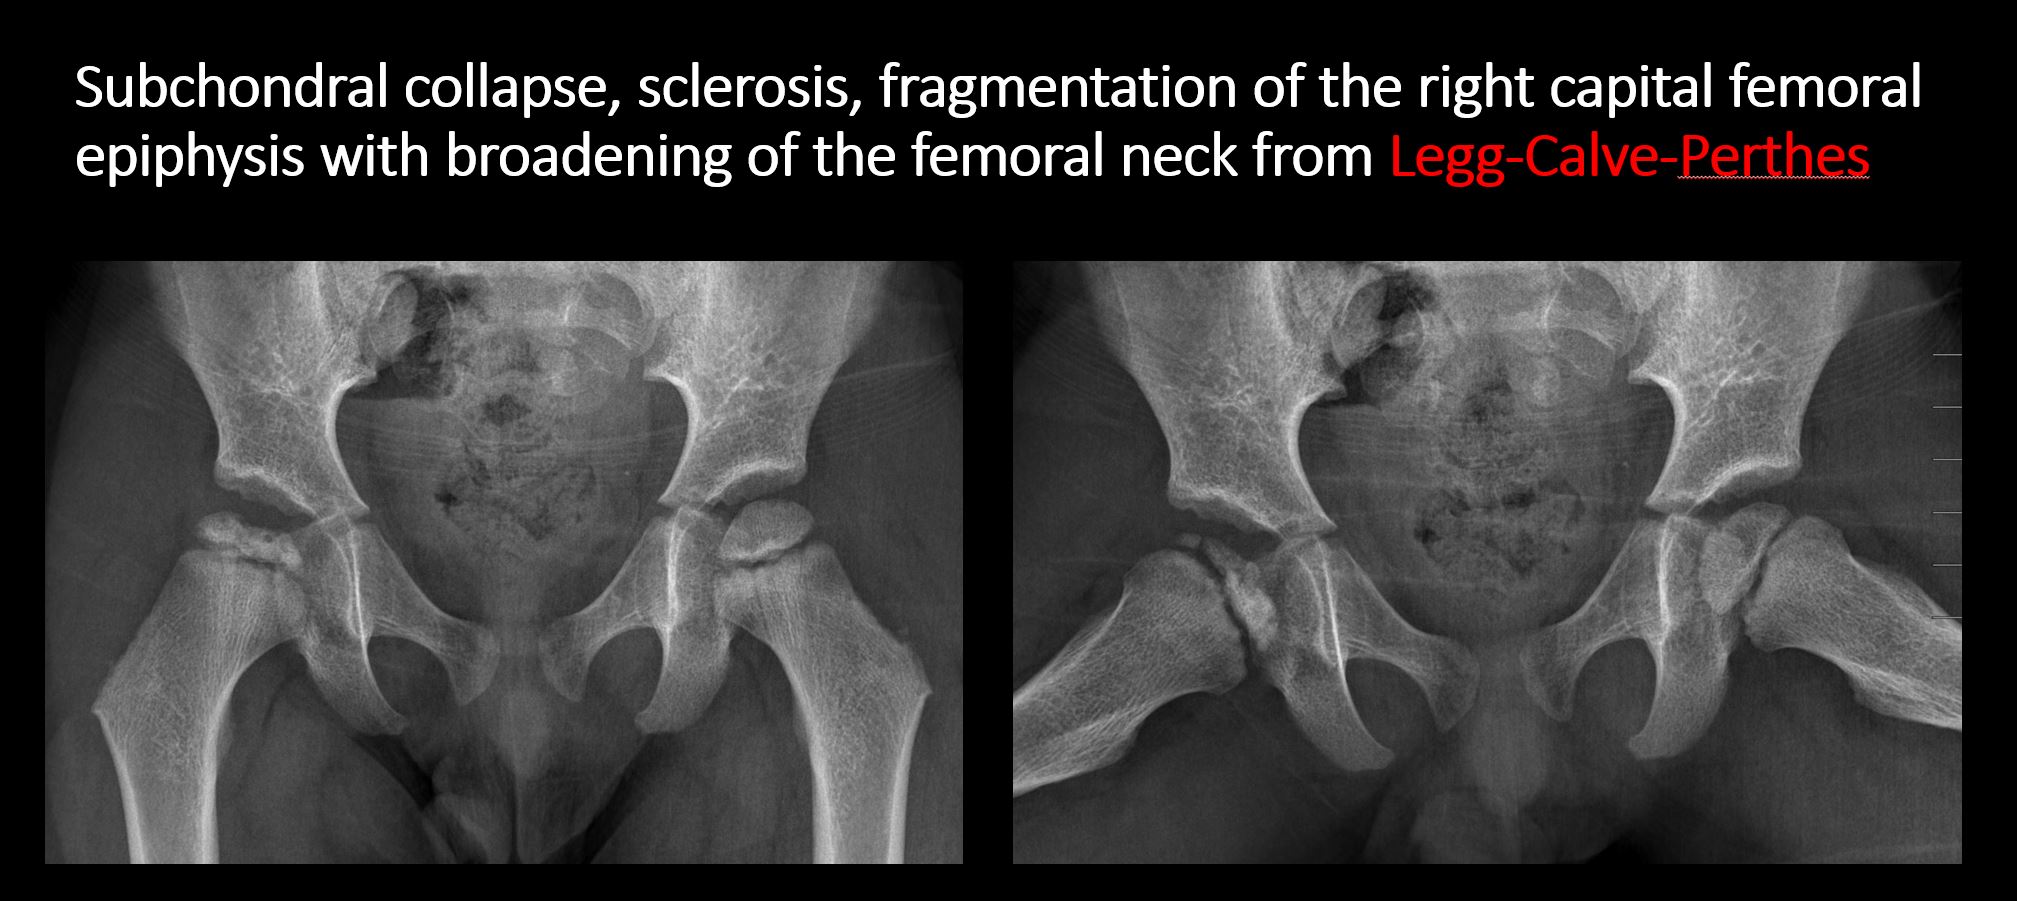

There is linear or irregular lucency, or increased density, cortical depression, flattening, or collapse, with or without cortical disruption or thickening, which may be from a compression or impaction fracture, stress or insufficiency fracture, osteonecrosis (e.g. Legg-Calve-Perthes), other fracture, or from growth recovery lines. [Yes/No]

The epiphysis or subchondral bone is fractured, interrupted, flattened, compressed, impacted, displaced, or otherwise abnormal. [Yes/No]